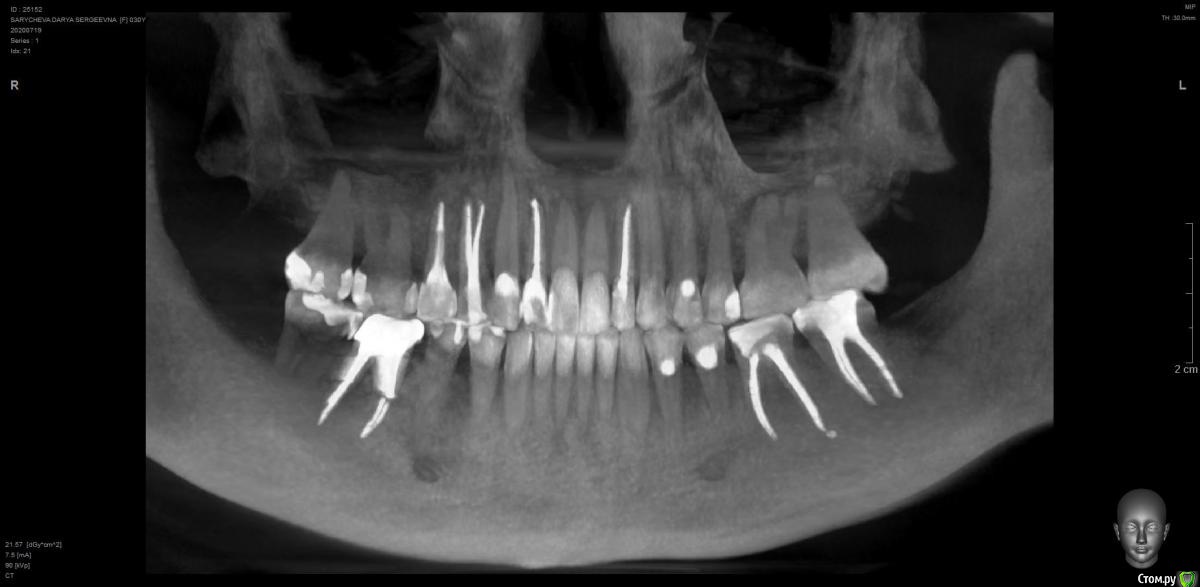

Добрый день. Всю беременность мучилась с зубами. Депульпировали 14 и 15, лечили кариес в 16 и 17. 3 месяца как болит 14 после депульпирования. Болит постоянно, ноет, иногда при хотьбе отдается. В какой-то момент я упросила очень хорошего стоматолога под микроскопом перелечить, но боль осталась. После родов сделала кт, говорят, что и 14 и 15 идеально пролечены, что там болит непонятно. Но есть гранулема в 12, сейчас ее лечим, но боль в 14 не дает покоя. Что делать и почему он может болеть? Уже готова его удалять, настолько измучилась, но жалко, если с ним правда все в порядке... Помогите, пожалуйста.